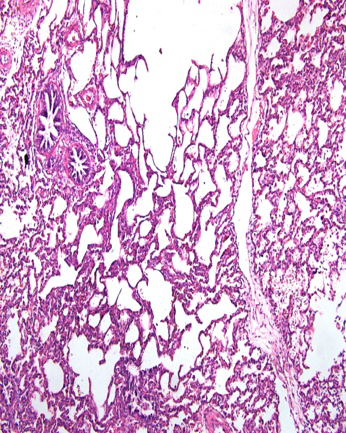

蓝耳感染早期肺形态图片,左面图基本可以认为是正常肺,可以很好的萎缩塌陷,右面的肺发病中晚期,这两种肺都是可以检出蓝耳病毒的,病毒感染早期有时候无法还无法形成肉眼可以鉴别诊断的临床症状,中期和晚期发病的猪的大体病变是有很重要的诊断意义,中图显微病变为轻度的间质性肺炎,显微病变可以很好的衡量发病与否

图片来源于蓝耳很不稳定场